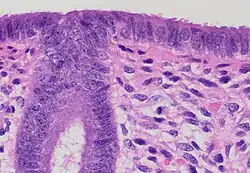

![]() Endometrium in the proliferative phase | |

The endometrium is the inner epithelial layer, along with its mucous membrane, of the mammalian uterus. It has a basal layer and a functional layer: the basal layer contains stem cells which regenerate the functional layer.[1] The functional layer thickens and then is shed during menstruation in humans and some other mammals, including other apes, Old World monkeys, some species of bat, the elephant shrew[2] and the Cairo spiny mouse.[3] In most other mammals, the endometrium is reabsorbed in the estrous cycle. During pregnancy, the glands and blood vessels in the endometrium further increase in size and number. Vascular spaces fuse and become interconnected, forming the placenta, which supplies oxygen and nutrition to the embryo and fetus.[4][5] The speculated presence of an endometrial microbiota[6] has been argued against.[7][8]

Structure

The endometrium consists of a single layer of columnar epithelium plus the stroma on which it rests. The stroma is a layer of connective tissue that varies in thickness according to hormonal influences. In the uterus, simple tubular glands reach from the endometrial surface through to the base of the stroma, which also carries a rich blood supply provided by the spiral arteries. In women of reproductive age, two layers of endometrium can be distinguished. These two layers occur only in the endometrium lining the cavity of the uterus, and not in the lining of the fallopian tubes where a potentially life-threatening ectopic pregnancy may occur nearby.[4][5]

- The functional layer is adjacent to the uterine cavity. This layer is built up after the end of menstruation during the first part of the previous menstrual cycle. Proliferation is induced by estrogen (follicular phase of menstrual cycle), and later changes in this layer are engendered by progesterone from the corpus luteum (luteal phase). It is adapted to provide an optimum environment for the implantation and growth of the embryo. This layer is completely shed during menstruation.

- The basal layer, adjacent to the myometrium and below the functional layer, is not shed at any time during the menstrual cycle. It contains stem cells that regenerate the functional layer,[1] which develops on top of it.

It is possible to identify the phase of the menstrual cycle by reference to either the ovarian cycle or the uterine cycle by observing microscopic differences at each phase—for example in the ovarian cycle:

| Phase | Days | Thickness | Epithelium |

|---|---|---|---|

| Menstrual phase | 1–5 | Thin | Absent |

| Follicular phase | 5–14 | Intermediate | Columnar |

| Luteal phase | 15–27 | Thick | Columnar. Also visible are arcuate vessels of uterus |

| Ischemic phase | 27–28 | Columnar. Also visible are arcuate vessels of uterus |